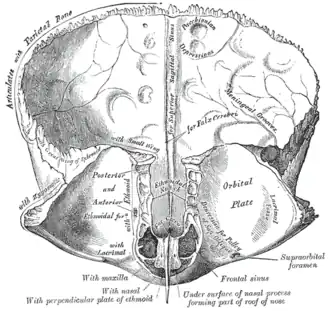

Diagrammatic representation of a section across the top of the skull, showing the membranes of the brain, etc. ("Arachnoid granulation" label is at top right.) | |

The arachnoid granulations may be lodged within granular foveae — small pits upon the inner surface of the cranial bones.[3][4]

Left parietal bone. Inner surface.

Frontal bone. Inner surface.